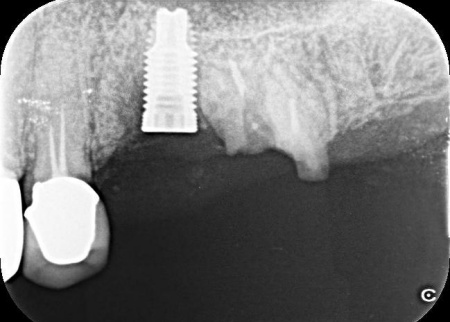

| 行ったご提案・治療内容 | 患者様には、折れた左上奥歯は温存ができず、歯根を抜く必要があることをお伝えしました。 そのうえで、希望されているインプラント治療を行うために必要な点を説明しています。 ・インプラント治療に必要な骨の量を確保するための「骨補填」を行う こちらに同意いただき、3ヶ月後からインプラント治療を始めることになりました。 まず、左上奥歯を抜きます。 3ヶ月後、顎の骨の状態が良好であることを確認し、インプラントを埋入する手術を実施しました。 |

治療中

治療後